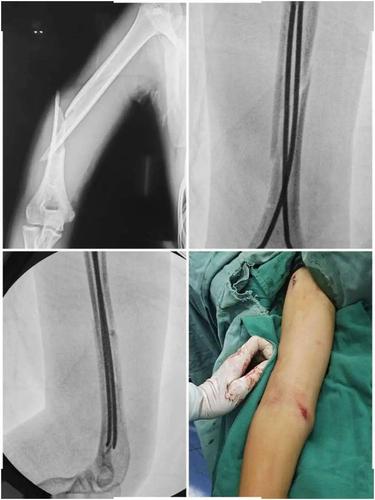

术精岐黄|11岁女孩手臂卷入洗衣机致骨折 医生微创手术巧复位

前臂双骨折

肱骨髁上骨折

青枝骨折

斜形骨折